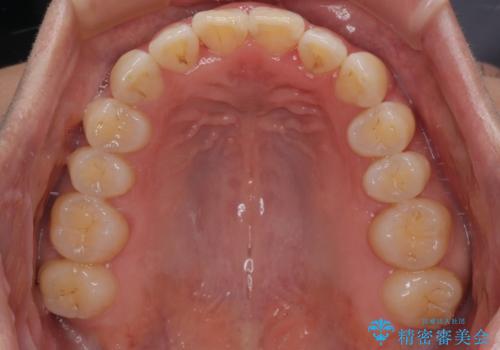

【モニター】飛び出した上顎前歯 補助装置を併用したインビザライン矯正治療

補助装置なしでも改善できる可能性はありましたが、補助装置で確実性を上げ、短期間できっちりと仕上げることができました。